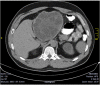

Case reports: We report two cases of huge (25cm and 20cm in diameter, respectively) echinococcal cysts located in the left liver, which presented as a large palpable mass causing compression symptoms. Diagnosis was established with CT scan showing a cystic mass with the characteristic daughter cysts and reactive layer (pericystic wall) consisting of fibrous connective tissue and calcifications. Both patients were treated radically with left hepatectomy and had uneventful postoperative course and no recurrence upon follow-up.